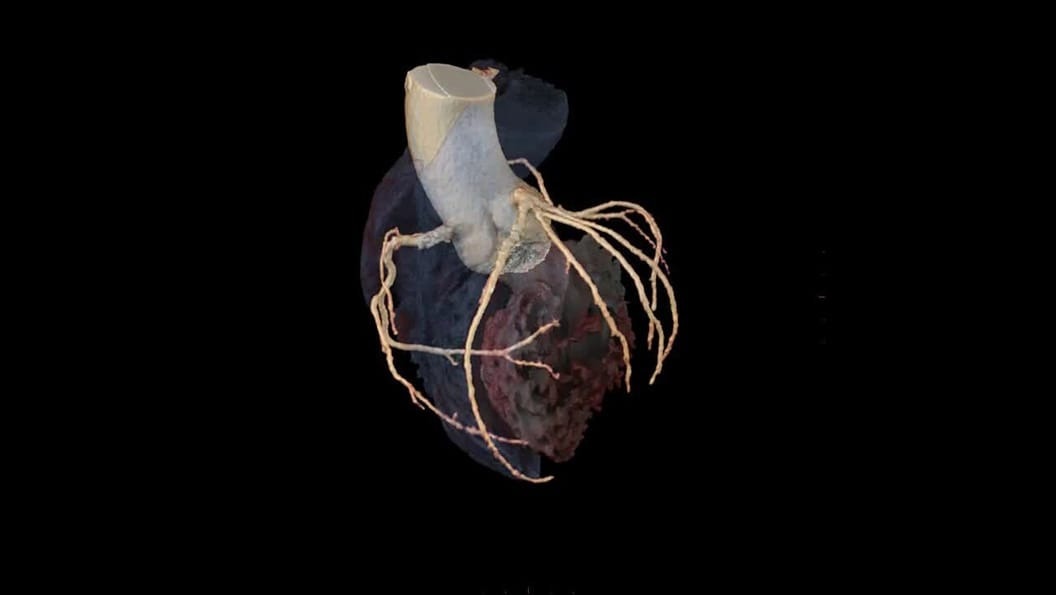

SnapShot Freeze 2

Automated whole heart motion correction, SnapShot Freeze 2 is an intelligent motion correction algorithm designed for automated whole heart motion correction, including coronary artery, valves, myocardium, chambers, and the great vessels motions.

1-ct-snapshot-freeze-2-whole-heart-motion-correction